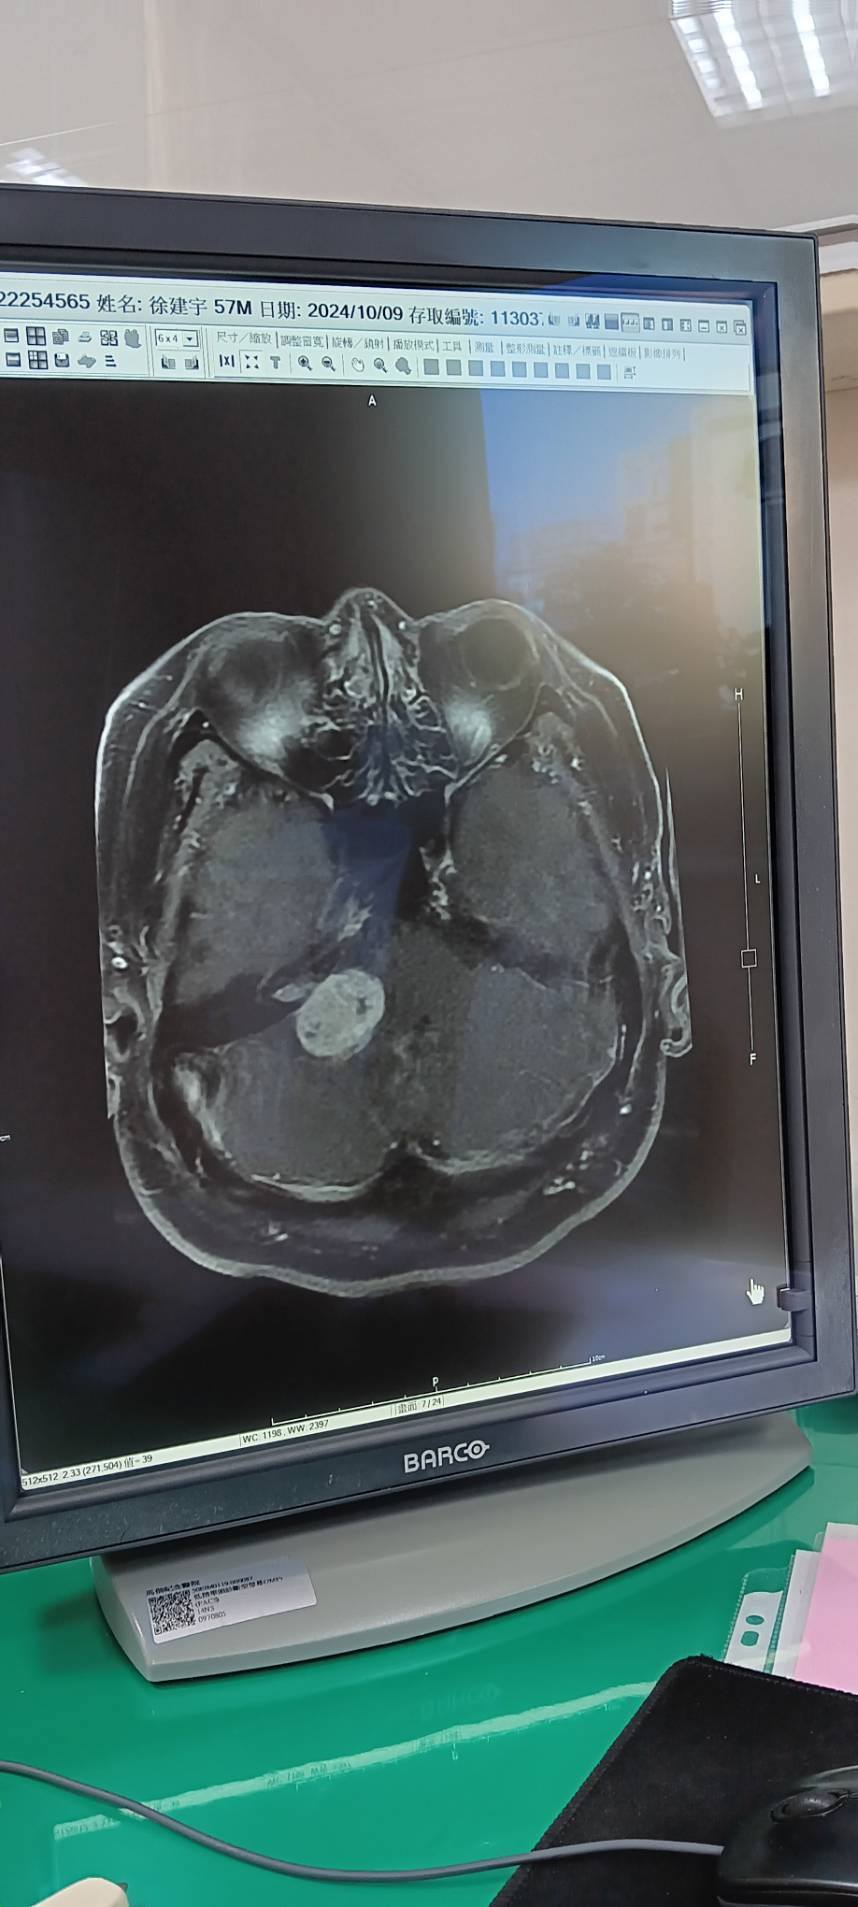

根據《今日新聞》報導,徐亨因長期承受龐大債務壓力,一度出現嚴重消瘦情形。某日他突然昏倒,緊急送往馬偕醫院就醫,經診斷發現罹患腦瘤並引發水腦症。由於病情危急,醫師立即為他進行手術,在體內植入三條導管,協助將腦部積水引流排出。不過腦瘤因位於神經系統重要位置,手術風險過高,目前僅能透過放射治療和藥物控制病情。